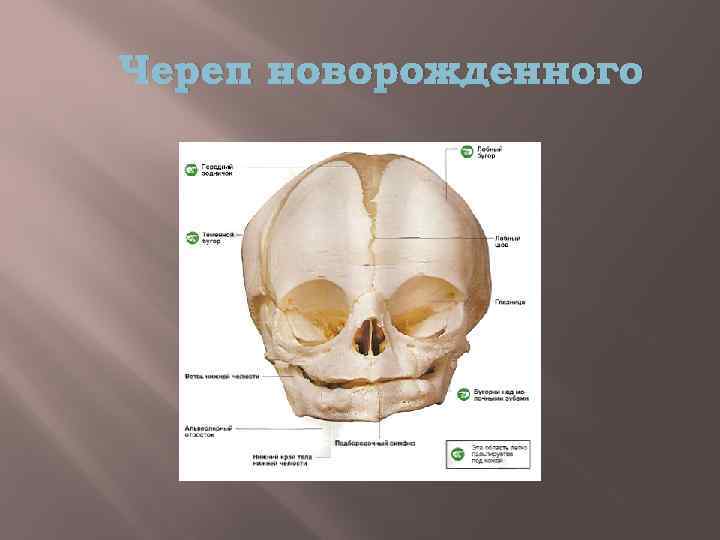

Анатомия детского черепа: Рентгеновские снимки и описание